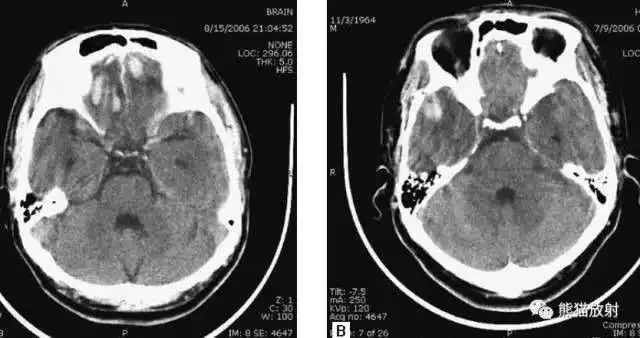

头部枪伤:

可见子弹轨迹,穿越大脑中线,

其毁灭性后果导致:

侧脑室积血,蛛网膜下腔出血,

脑积水(侧脑室颞角扩大),

小脑幕疝(脑干周围基底池消失或不对称)。